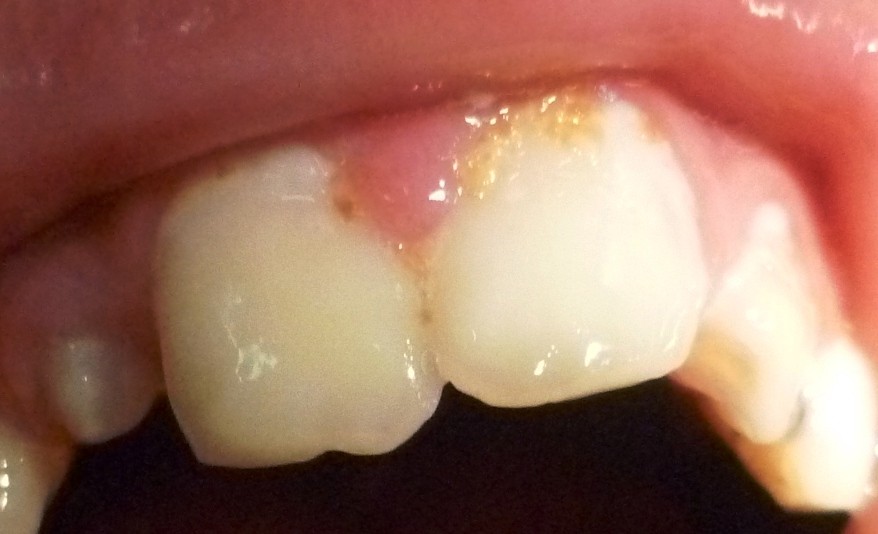

This paper presents a 12-year-old male patient with XXXXY syndrome, who was treated under general anesthesia twice due to mental retardation and uncooperative behavior. The general and dentofacial manifestations of XXXXY syndrome where present.The child had to be treated as as an emergency case both times due to severe pain and abcesses. Several teeth were severely decayed and had to be extracted that led to severe anodontia as there were no secondary dentition to follow. This case emphasises the importance of regular dental care, good nutricion and monitoring of dental development in children with XXXXY syndrome.